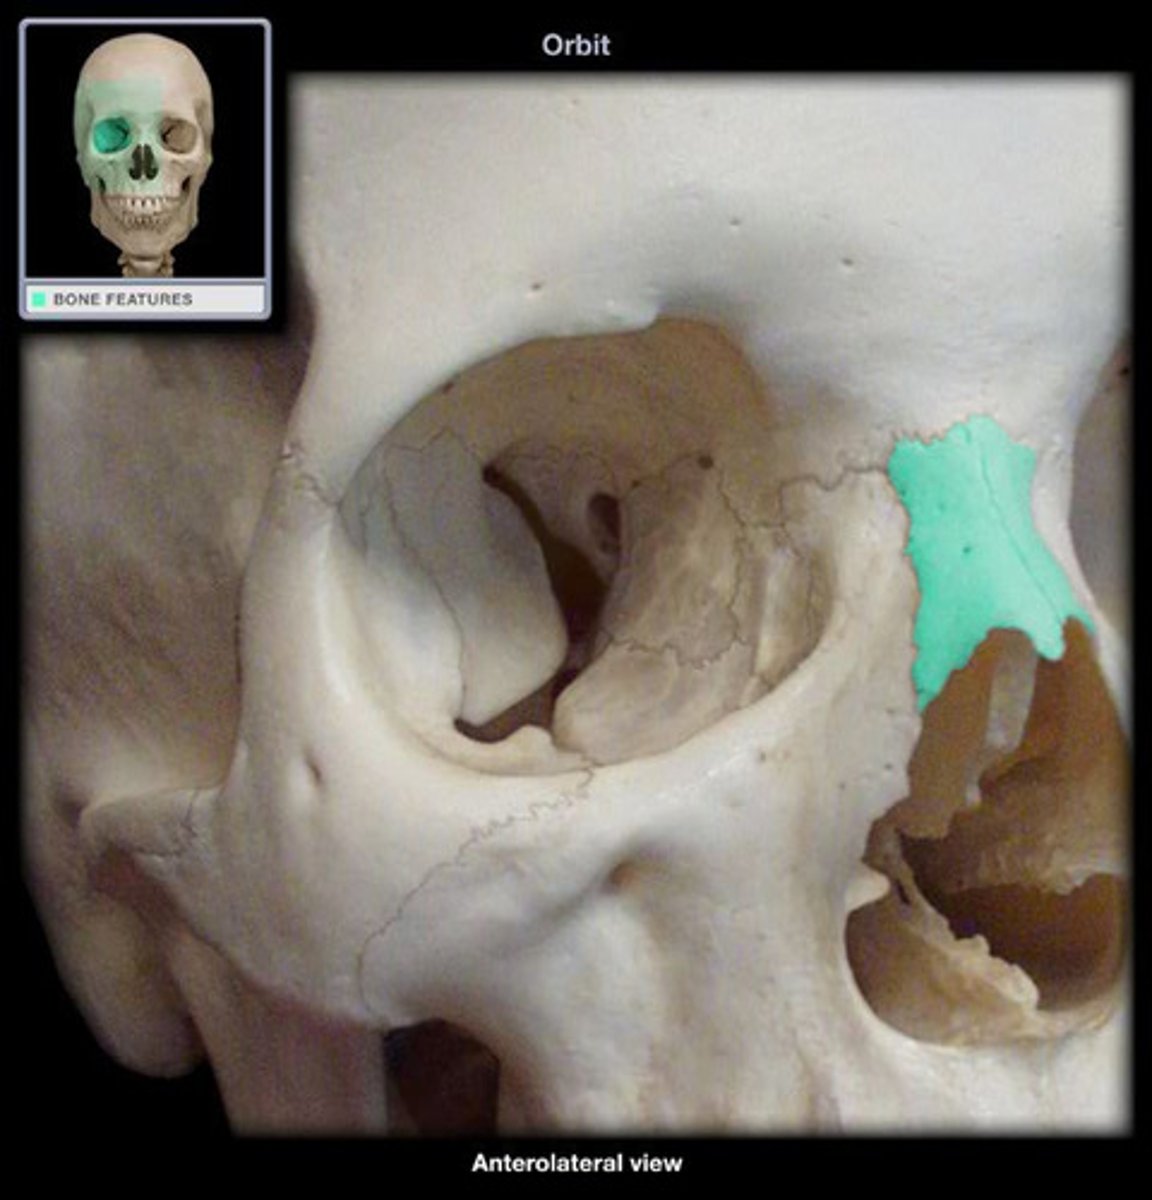

- Lacrimal bones

- each bone contains a lacrimal foramen though which the tear duct passes through

SMALLEST FACIAL BONE

what is this and what does it do ?